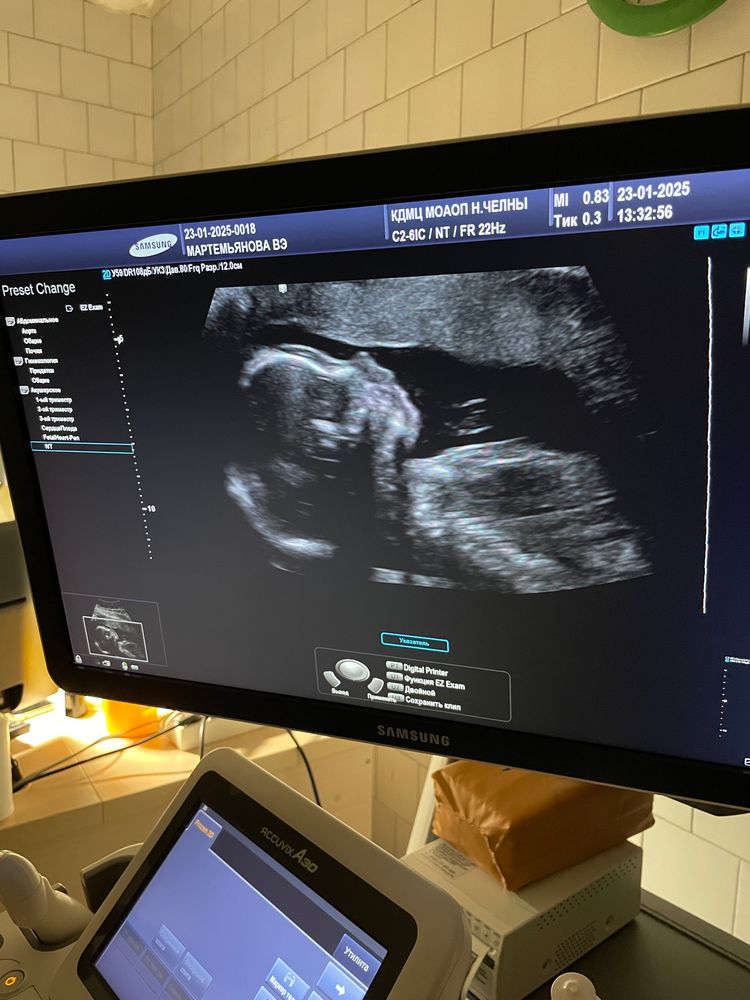

2 скрининг, 19 недель 1 день, полет нормальный)

Даже написать то нечего. Все у него прекрасно, все по сроку. Весит 295 грамм, что не может не радовать, ибо у меня гсд на инсулине. Отек плаценты, который был в 17 недель, прошёл. Следующий чек-поинт в 25 недель)

Наш курносик🥰